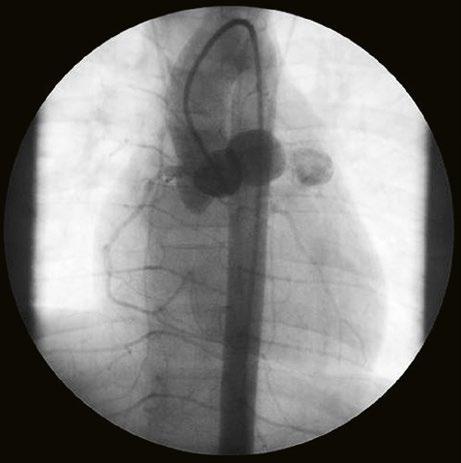

Supravalvární pulmonální stenóza a stenózy větví plicnice bývají součástí komplexních VSV (např. Fallotovy tetralogie) nebo syndromů (Williamsův syndrom, syndrom Noonanové, syndrom vrozené rubeoly, Alagillův syndrom aj.) (Obr. 45.39). Získané stenózy větví plicnice, ale i úplný uzávěr větve plicnice můžeme vidět po spojkových operacích podle BlalockaTaussigové (Obr. 45.40, Obr. 45.41). Pro zobrazení supravalvárních a periferních stenóz plicnice je optimální CT angiografie (Obr. 45.40, Obr. 45.41, Obr. 45.42, Obr. 45.43).

Obr. 45.40 CT angiografie, 8mm stenóza a deformace levé větve plicnice (šipka) po spojkové operaci podle BlalockaTaussigové v dětství LPA – levá větev plicnice, PA – kmen plicnice, RPA – pravá větev plicnice

Obr. 45.41 Uzávěr levé větve plicnice jako následek provedené spojky podle BlalockaTaussigové v dětství, CT angiografie